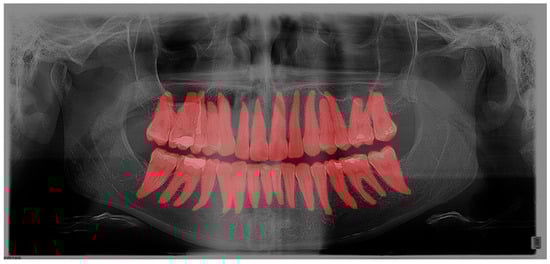

As a second layer, after outlining the teeth, each filling, crown, bridge, implant, endodontic filling, and tooth build-up was marked (Figure 2).

Figure 2. Segmentation of dental interventions on OPG in the GIMP program.